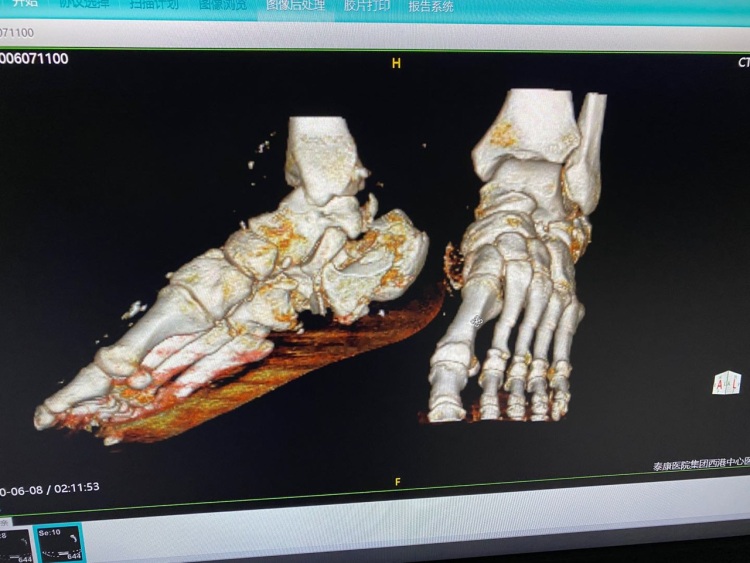

请花5分钟看完这个帖子,今日凌晨三点左右,一工地遇到一伙小偷,被李师傅看到于是他跟小偷周旋之下被一伙小偷从还没装好的电梯推下去,被摔成重伤,由于李师傅一人在柬务工,没有亲人,工友们把他送到西港泰康中心医院,由于李师傅昏迷不醒,我们医院先救人,把伤口包扎好,但由于李师傅双脚骨折需要立即做两个手术,就在这时一位素不相识的中国同胞患者在隔壁病房输液,听说这个事,就说了一句话救人要紧,马上差人从银行取了5000美金帮助这位李师傅缴纳了手术费用,我们全院代表李师傅很感谢这位中国老板,这位中国老板不愿留下姓名,在这里真的很感谢这位中国同胞,泰康医院也是本着救人为本,帮助每一位患者,一切以病人为中心,希望大家把爱传承下去,尽所能帮组身边需要帮助的同胞,

情况属实!李先生为工地材料看守人员,在追击小偷时,被小偷推入电梯井,深受重伤,目前正在泰康医院手术中。为伤者李先生垫付五千美元的好心人,不愿意留单位和个人名字。做好人好事不留姓名,经了解爱心同胞为江苏人曹先生,他的助理辽宁人宋先生。西港正能量!感谢曹先生、宋先生大爱!